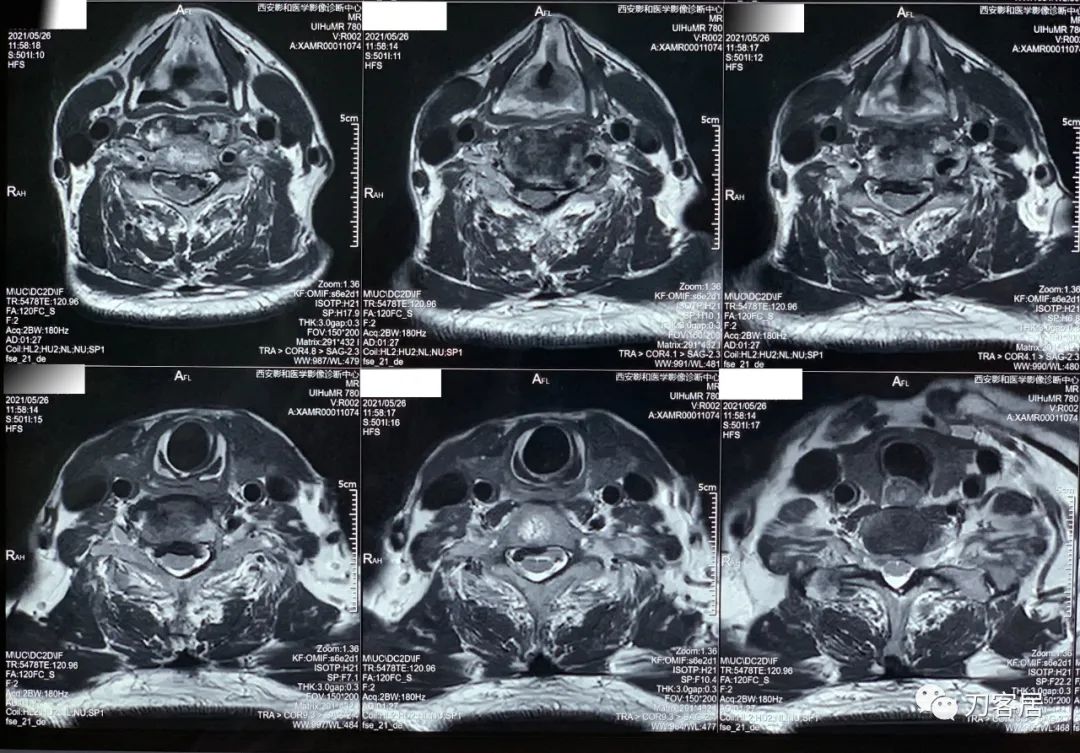

20210526-颈椎MRI经椎间盘横截面扫描。